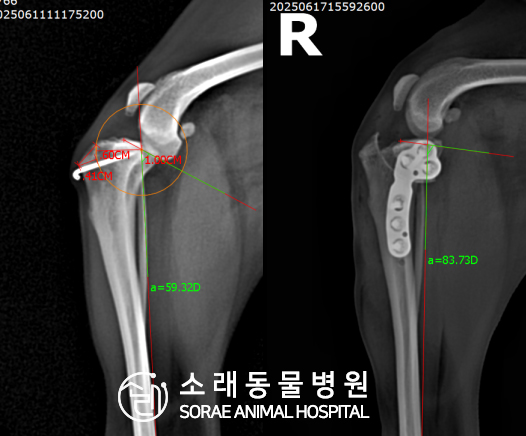

계산식으로 사전에 계획해두었던 플랜에 따라 경골을 절제하고

플레이트와 스크류를 사용하여 임플란트를 적용해 주었습니다.

반대 방향으로 밀려나 어긋나있던 대퇴골과 정강이가

제 자리를 찾으면서 무릎의 각도가 교정된 것을 확인할 수 있습니다